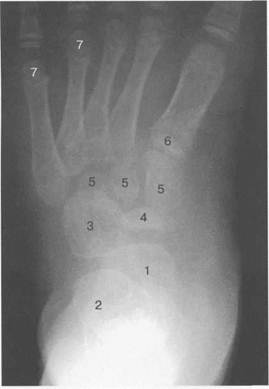

Рис. 19.137. Рентгенограмма стопы (1 год).

1 — таранная кость; 2 — пяточная кость; 3 — кубовидная кость; 4 — ядро ладьевидной кости; 5 — плюсневые кости.